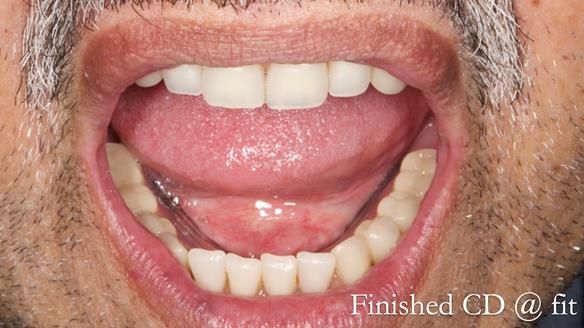

Welcome to Newsletter 62. In this edition, I walk through the process of removing 5 upper anterior teeth, adding to an existing upper RPD, followed by creating and fitting metal based complete dentures for Rafique, a 71 year old man.

The detailed clinical situation and treatment process are outlined below, with clinical work provided by me and technical work by Rowan Garstang. The treatment spanned 12 months, involving removing 5 upper anterior teeth, adding to an existing upper RPD, followed by creating and fitting metal based complete dentures.

Rafique adapted superbly to the complete dentures not only because they fitted well. He had a positive approach to the treatment and put the effort in to work with the new dentures rather resisting them. I can’t stress how important this is for success with dentures.